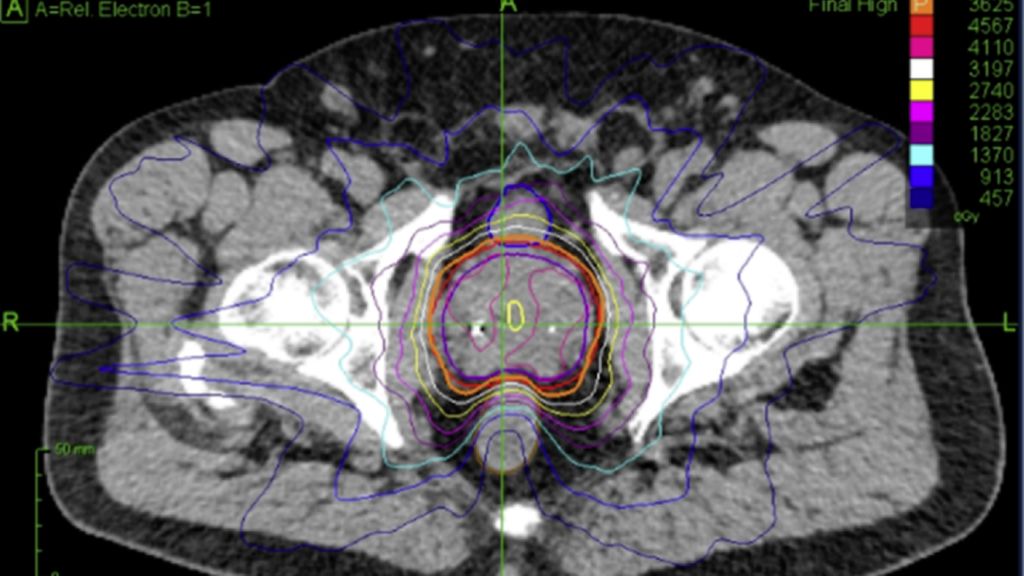

Fig. 1: Dose distribution for prostate cancer patients treated on robotic SBRT platform (Cyberknife)